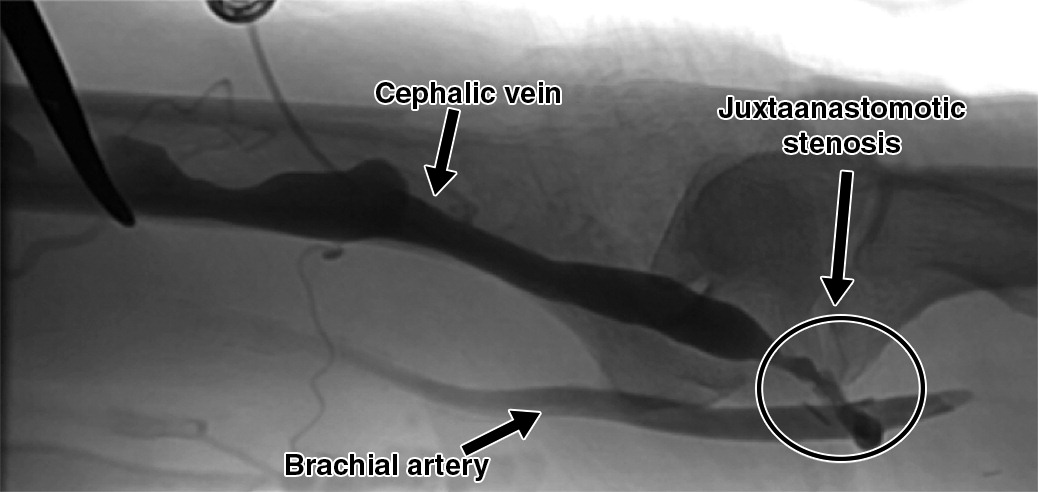

Stenosis and thrombosis are often categorized into inflow and outflow problems based on their anatomical location and physiologic effects. Inflow complications arise from reduced blood entering the access. This is usually due to an arterial lesion or a lesion at the juxtaanastomotic portion of the fistula. Outflow complications stem from obstruction of venous return. The lesion can be in the outflow tract emptying the extremity or in the central veins.

Stenosis typically occurs at sites of high turbulence, such as the venous outflow tract or central veins. Juxta-anastomotic stenosis (JAS) is the most common lesion in AVFs, typically located within 3-4 cm of the arterial anastomosis. Varying lengths of focal and diffuse stenosis can occur.

Clinically, stenosis is often detected through signs such as hyperpulsatility or diminished augmentation of the pulse. For example, a hyperpulsatile AVF indicates significant outflow resistance, while poor augmentation of the pulse may suggest inflow stenosis. The arm elevation test can also help distinguish stenotic from normal segments; in significant outflow stenosis, the distal vein remains distended when the arm is raised. Imaging modalities confirm stenosis and guide treatment. Duplex US is a preferred noninvasive method, while angiography provides definitive visualization of the stenotic segment and is often used during intervention. For a detailed description of physical exam findings and diagnostic approaches, please refer to Surveillance and Diagnostics and Imaging.